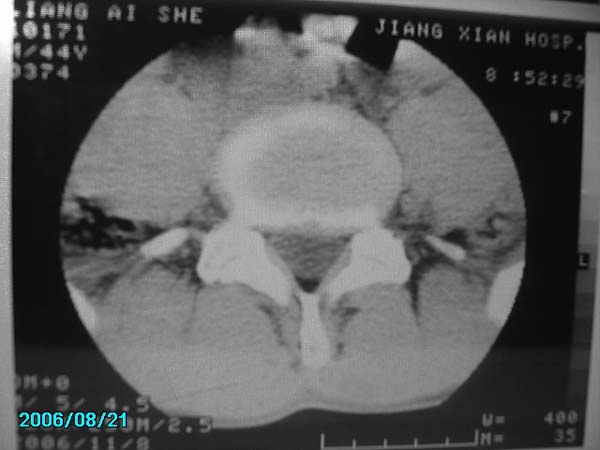

男,40岁,腰疼半年

腰4-5椎间盘后缘变平直,可考虑椎间盘轻度突出。余未见异常。

l4/5椎间盘膨出。

腰4-5椎间盘轻度突出。余未见异常。

腰椎侧弯,l4-5椎间盘膨出。

腰4-5、腰5-骶1椎间盘后缘变平直,可考虑椎间盘轻度突出。余未见异常

除有第3-5腰椎椎体后缘中央血管沟显示外,诸椎间盘比较正常。我也象13081830109战友那样看见了指纹,呵呵。